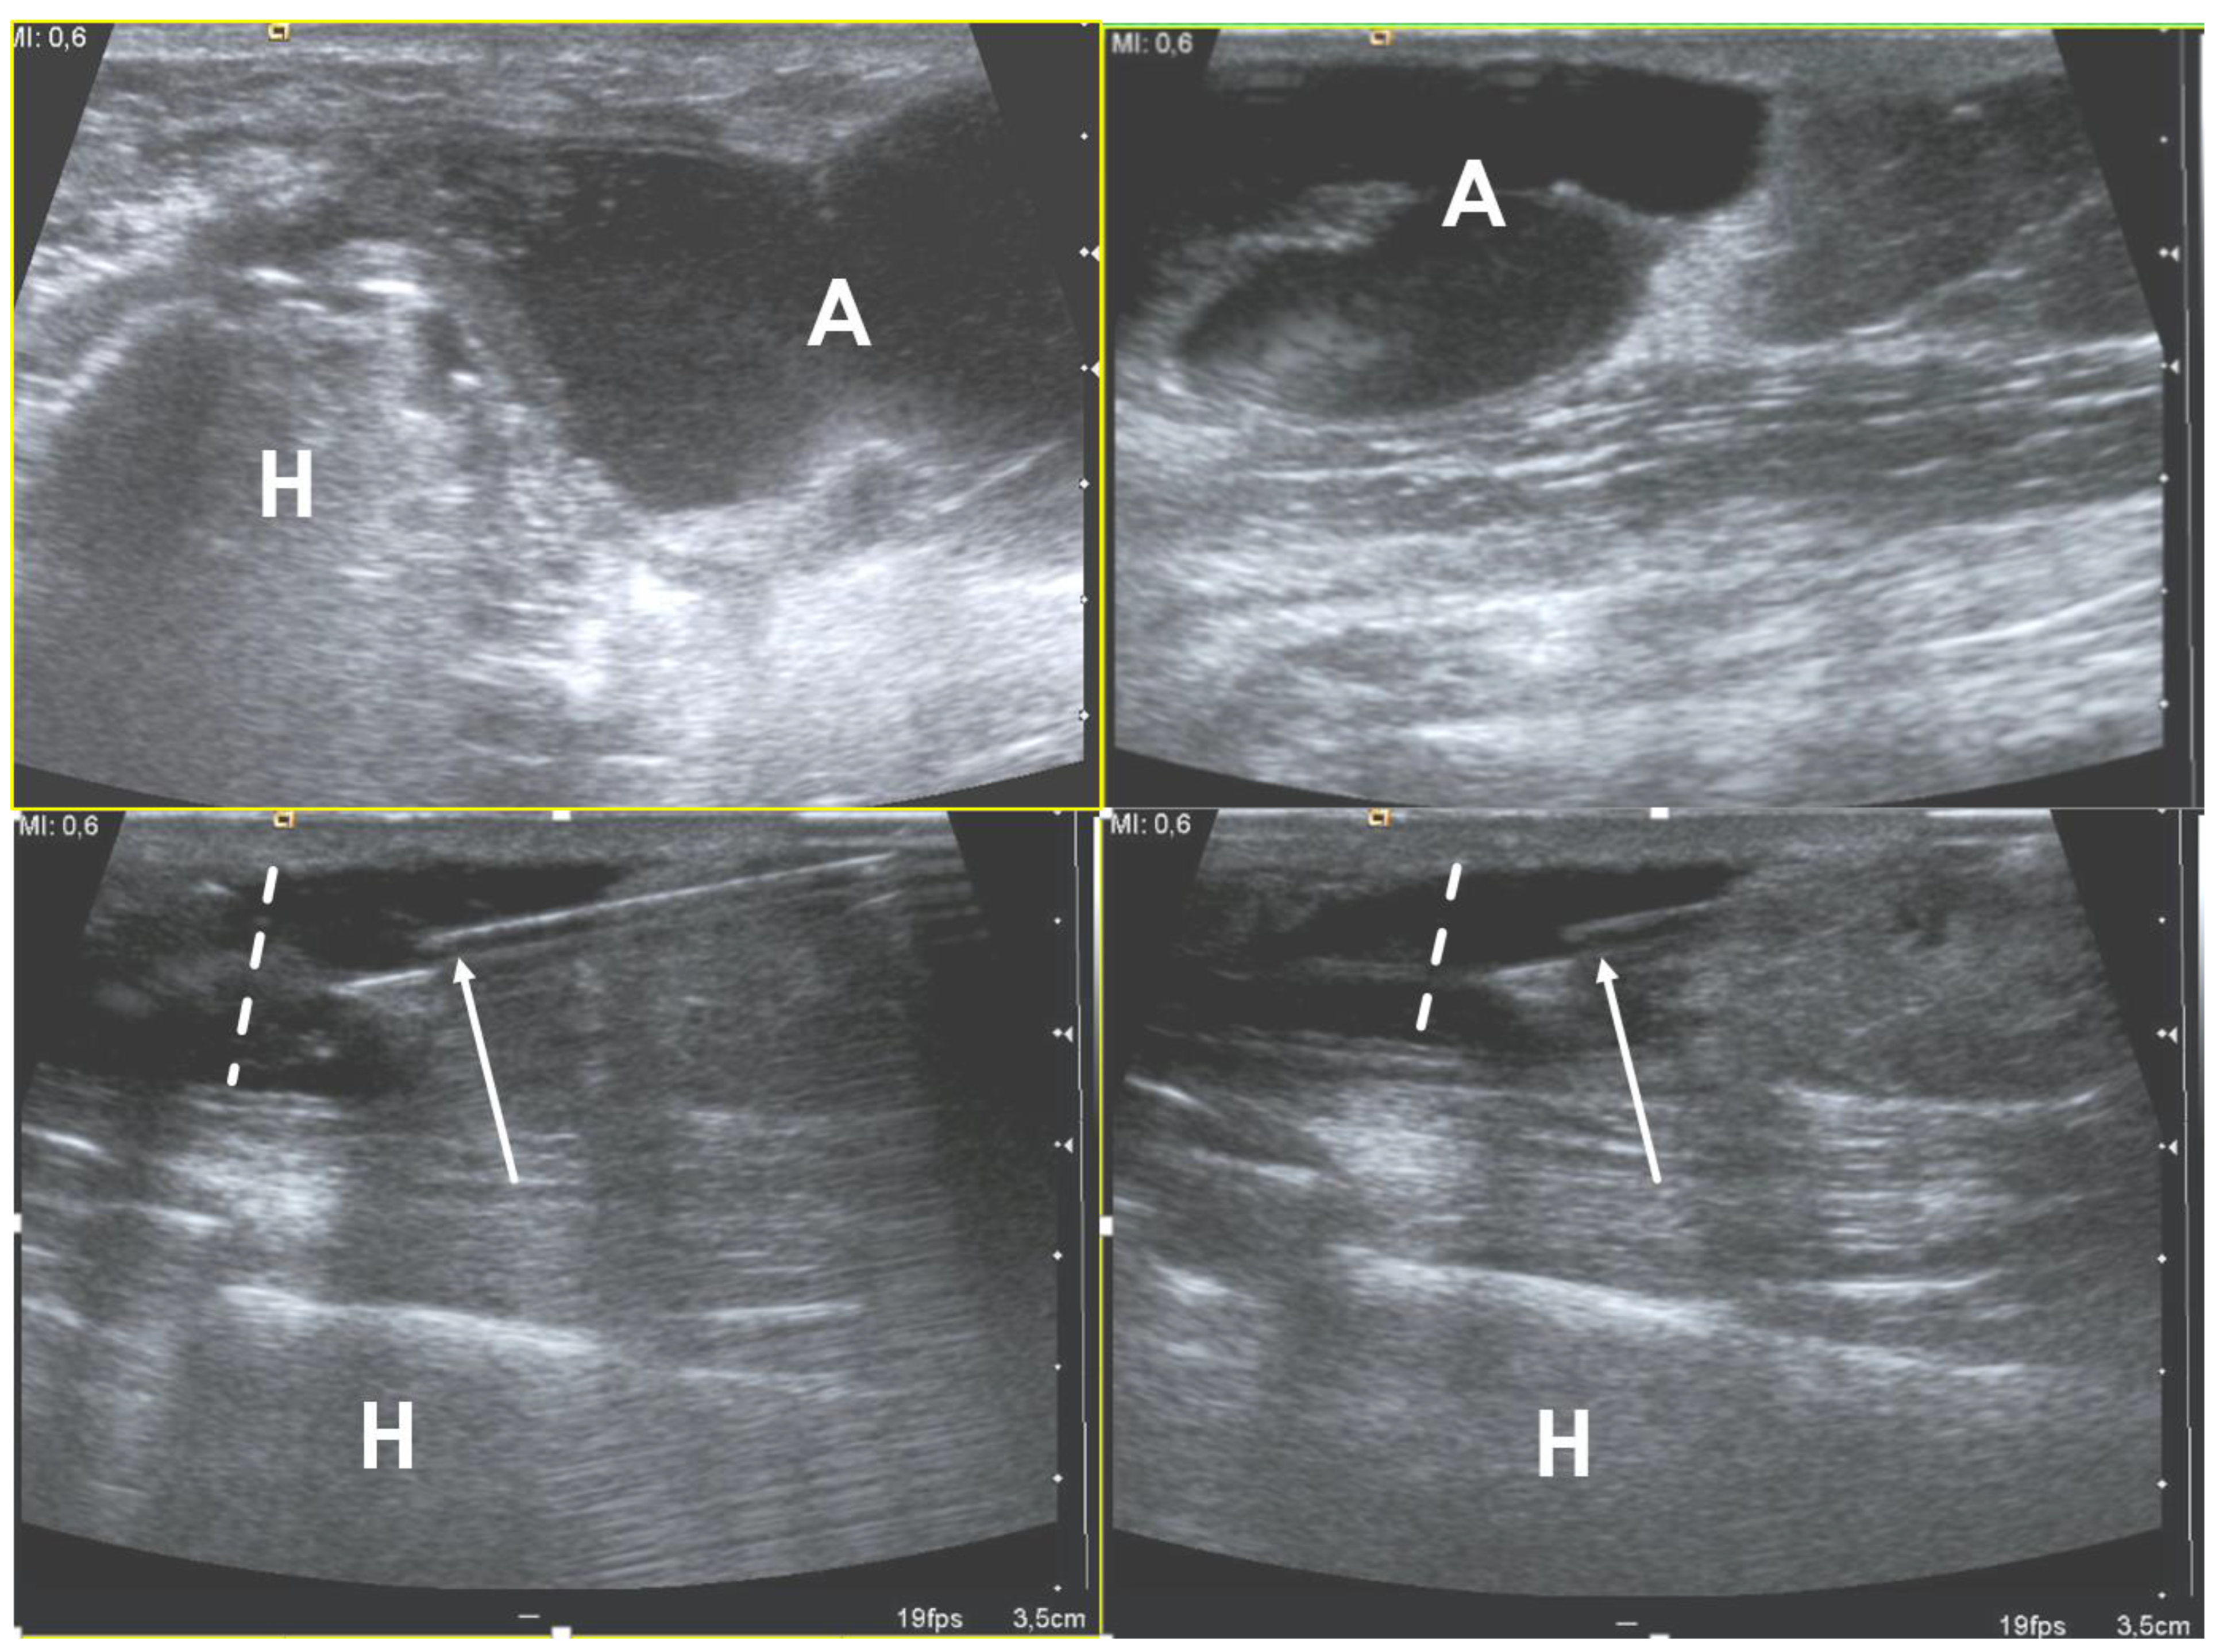

2.4. Abscess

- Bureau, N.J.; Chhem, R.K.; Cardinal, E. Musculoskeletal infections: US manifestations. Radiographics 1999, 19, 1585–1592. [Google Scholar] [CrossRef] [PubMed]

- Craig, J.G. Infection: Ultrasound-guided procedures. Radiol. Clin. N. Am. 1999, 37, 669–678. [Google Scholar] [CrossRef]

- Loyer, E.M.; Kaur, H.; David, C.L.; DuBrow, R.; Eftekhari, F.M. Importance of dynamic assessment of the soft tissues in the sonographic diagnosis of echogenic superficial abscesses. J. Ultrasound Med. 1995, 14, 669–671. [Google Scholar] [CrossRef] [PubMed]